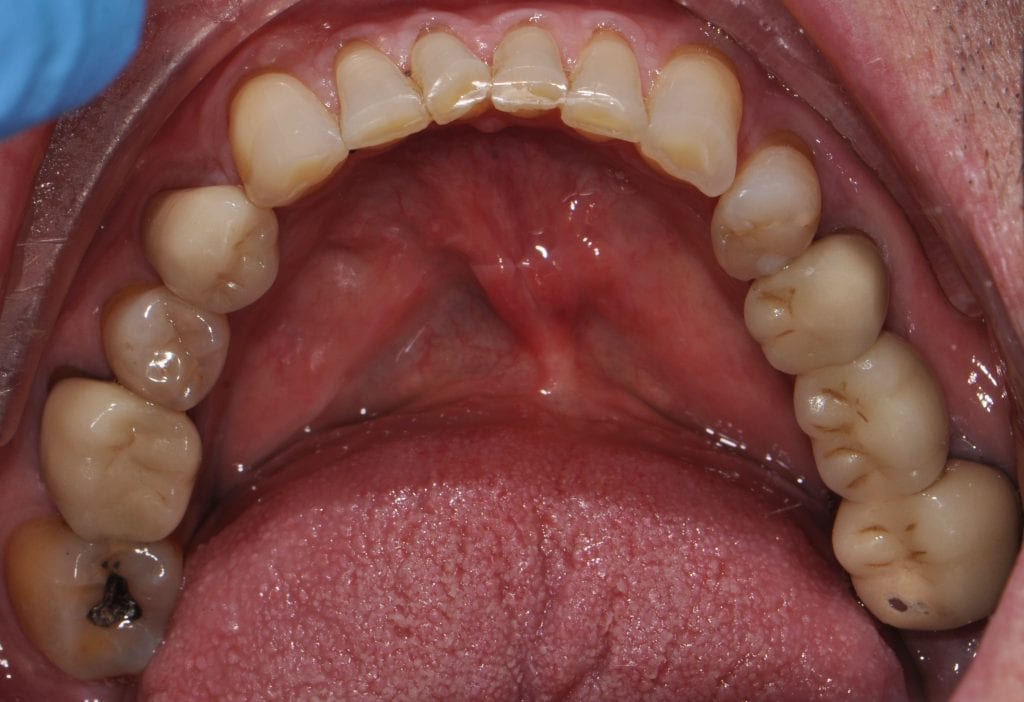

Pre-existing restorations that warranted replacement with an increase in vertical dimension.

Pre-existing restorations that warranted replacement with an increase in vertical dimension. The upper and lower arch were captured with the medit I500 and articulated together with enough clearance to accommodate new restorations and to restore the patient to an ideal tooth position.